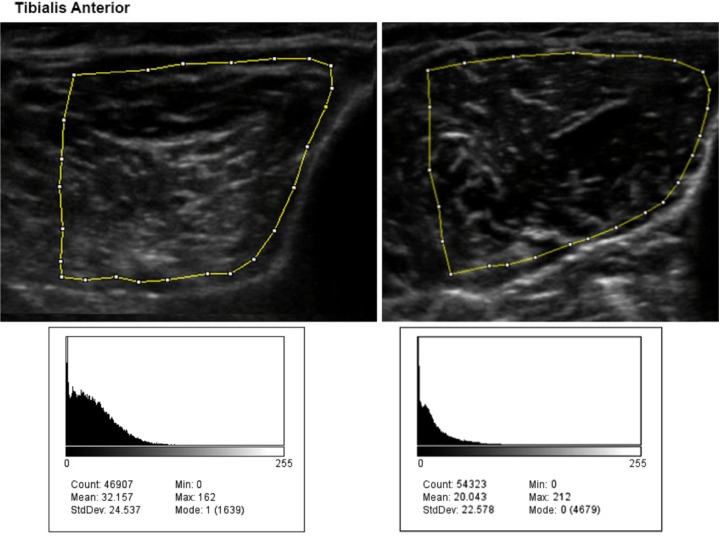

Methods: This study was conducted on 17 patients recently diagnosed with biopsy inflammatory myopathies (12 dermatomyositis, 5 polymyositis) compared with 17 age- and gender-matched healthy control adults. All patients underwent clinical assessments, including manual muscle testing, hand-held dynamometry, and muscle ultrasound evaluations, including thickness and echo intensity in predefined muscle groups.

Results: The disease duration was seven months (interquartile range: 3 to 11 months). Except for the biceps and gastrocnemius, patients' muscles had significantly higher echo intensity and lower thickness than the control group. The echo intensity sum-score manifested the highest area under the curve compared to the sum-scores of other variables (echo intensity vs manual muscle testing: Area under curves-difference=0.18, P<0.01; echo intensity vs dynamometry: Area under curves-difference=0.14, P=0.02; echo intensity vs thickness: Area under curves-differences-difference=0.25, P<0.01).

Conclusion: The echo intensity of muscles differed significantly between healthy individuals and patients with inflammatory myopathies and may serve as a useful diagnostic biomarker.